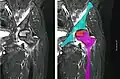

X-ray images of avascular necrosis in the early stages usually appear normal. In later stages it appears relatively more radio-opaque due to the nearby living bone becoming resorbed secondary to reactive hyperemia.[2] The necrotic bone itself does not show increased radiographic opacity, as dead bone cannot undergo bone resorption which is carried out by living osteoclasts.[2] Late radiographic signs also include a radiolucency area following the collapse of subchondral bone (crescent sign) and ringed regions of radiodensity resulting from saponification and calcification of marrow fat following medullary infarcts.

Radiography of avascular necrosis of left femoral head. Man of 45 years with AIDS.

Nuclear magnetic resonance of avascular necrosis of left femoral head. Man of 45 years with AIDS.